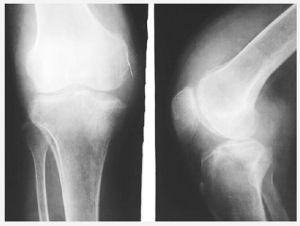

蹲走實驗8.X線檢查:拍照X線正側位片,雖不能顯示出半月板損傷情況,但可排除其他骨關節疾患。膝關節造影術對診斷意義不大,且可增加病人痛苦,不宜使用。